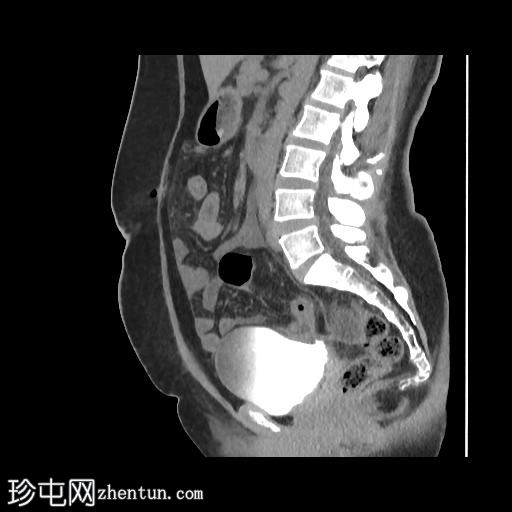

矢状位增强扫描(门静脉期)

矢状位肾盂排泄期

CT扫描显示:

左侧膀胱后外侧壁完全撕裂,造影剂外渗至盆腔

盆腔内可见少量积液

腹膜脂肪条索状改变,腹膜反折增厚强化,提示盆腔腹膜炎

腹腔镜

子宫切除术后医源性膀胱损伤伴盆腔腹膜炎的CT表现。